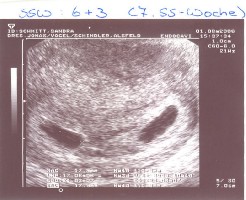

ES SIND ZWILLINGE!!!!!

Geburt von Lucca und Lennis am 4.2.07 in SSW 29+2